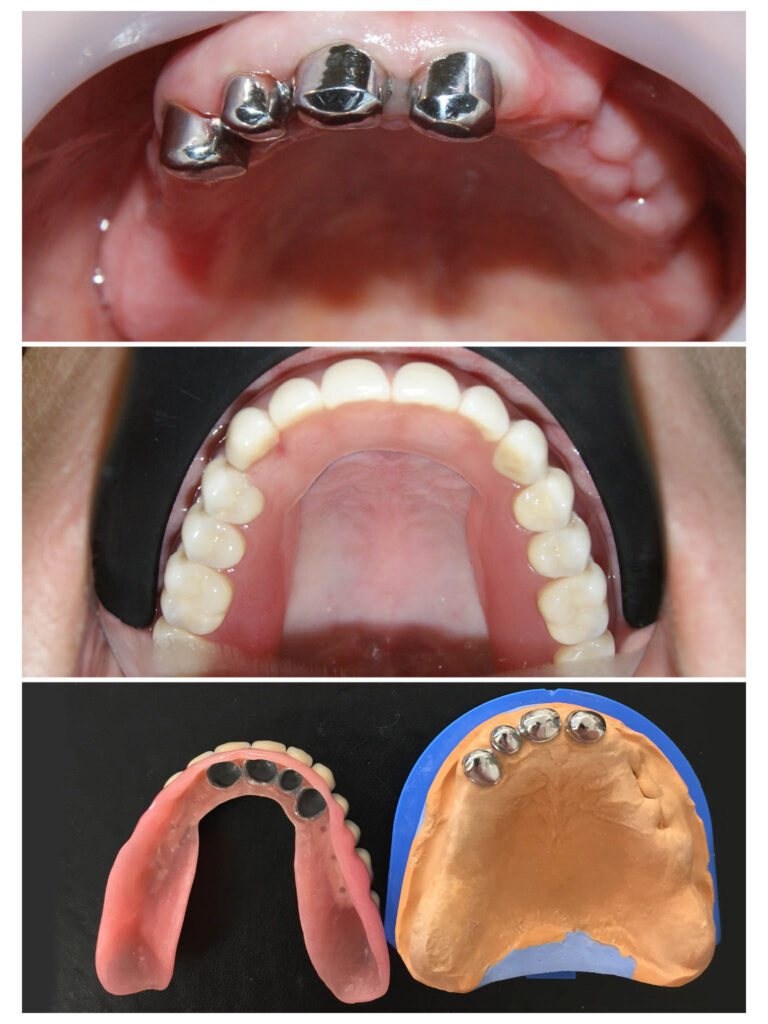

Lucrare fixată pe dinți împreună cu proteză scheletată mobilizabilă = soluția de lux pentru dinți puțini

Proteza telescopată și proteză scheletată aplicate pe dinții tratați corect! Execuția riguroasă oferă stabilitate excelentă.